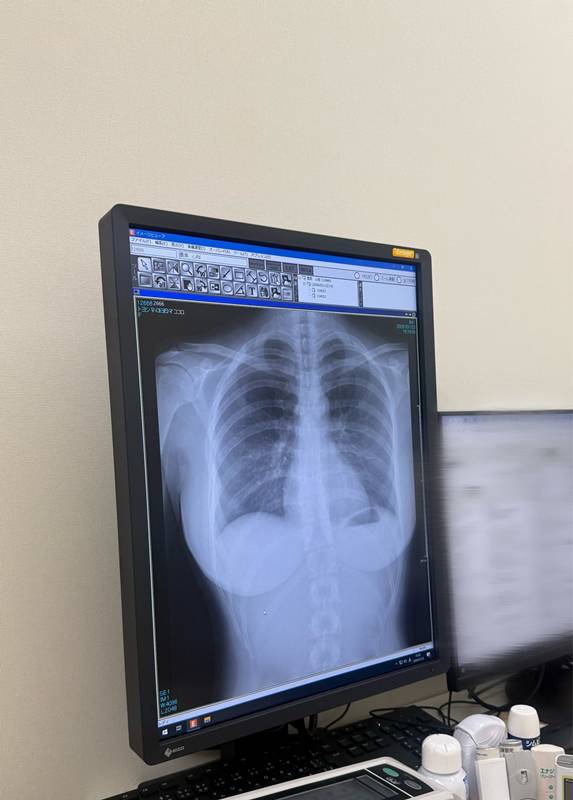

เมื่อวันที่ 23 มกราคม 2569 โคโคโระ โทโยชิมะ (Cocoro Toyoshima) นักแสดงและนางแบบสาวกราเวียร์ของญี่ปุ่น ได้สร้างความตกตะลึงฮือฮาบนโลกออนไลน์ หลังจากเธอโพสต์ภาพถ่ายเอกซเรย์ "ปอด" ของเธอ โดยบอกว่า ปอดของเธอปกติดีไม่มีปัญหา แต่ทำให้โซเชียลแตกตื่นและกลายเป็นไวรัลร้อนแรงชั่วข้ามคืน ทำเอาแต่ละคนหลุดโฟกัสไปตาม ๆ กัน

ในภาพถ่ายดังกล่าว นางแบบสาวโคโคโระ ได้บันทึกภาพถ่ายจากหน้าจอคอมพิวเตอร์ในห้องตรวจทางการแพทย์ โดยเผยให้เห็นผลการตรวจเอกซเรย์บริเวณช่วงบน ซึ่งผลการตรวจออกมาว่า ปอดของเธอมีสุขภาพดี โดยเธอเขียนแคปชั่นสั้น ๆ ว่า "ปอดสะอาด"

โพสต์ดังกล่าวได้รับความสนใจและกลายเป็นไวรัลอย่างรวดเร็ว เพียงแค่ 1 วันก็มีผู้เข้าไปชมมากกว่า 24.6 ล้านวิว พร้อมทั้งเข้าไปคอมเมนต์แสดงความคิดเห็นแพ้เสียงในหัวมากมาย